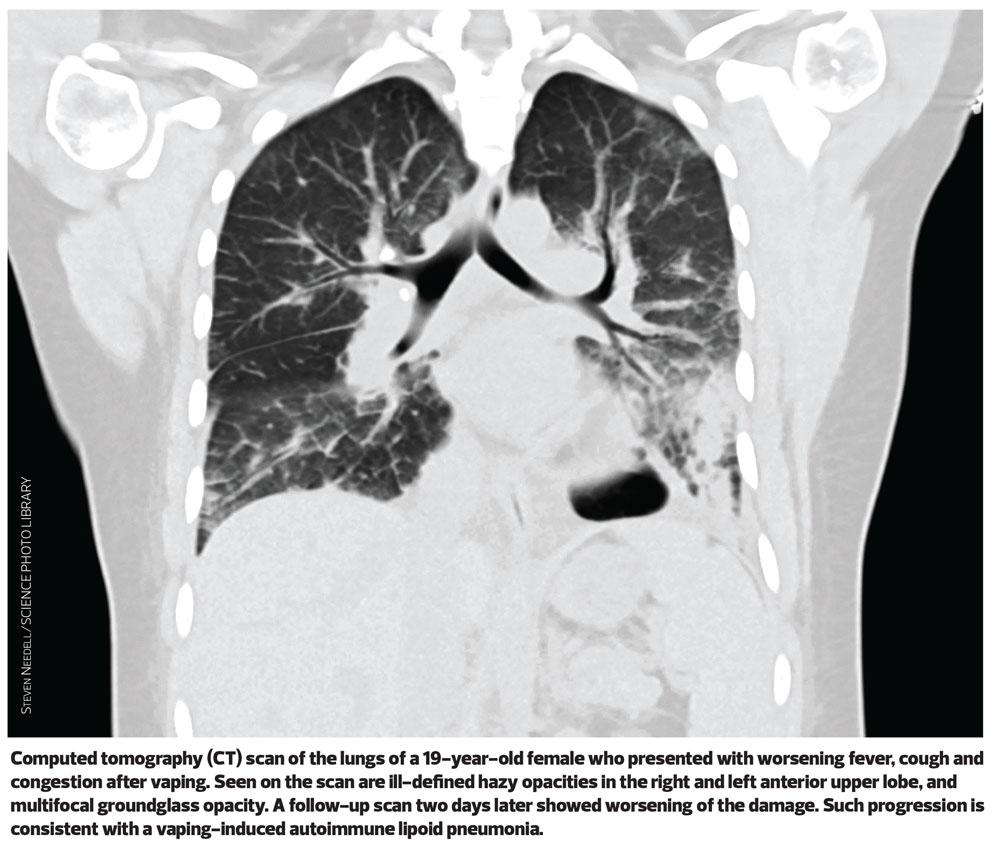

The Centers for Disease Control and Prevention (CDC) says that in most cases, patients reported a gradual onset of symptoms including breathlessness, breathing difficulties and chest pain.1 Patients have been found to have abnormalities on chest imaging, including lipoid pneumonia – an inflammatory response to the presence of lipids in the alveoli typically caused by aspiration of oil-based products.2